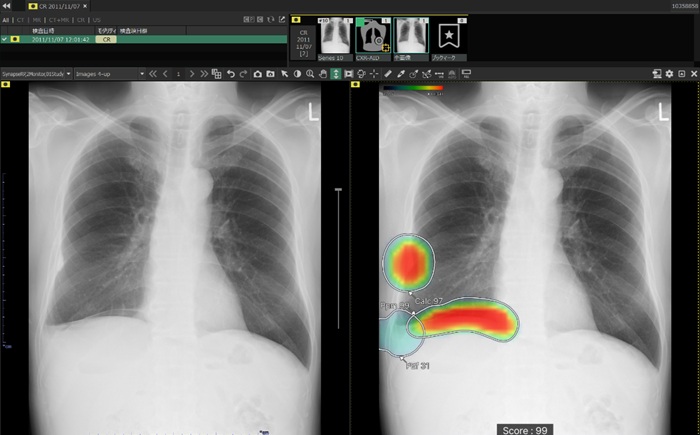

「CXR-AID」は、胸部X線画像をAI(人工知能)で自動解析し、病変の存在が疑われる領域を検出・マーキングして見落とし防止を支援するソフトウエア。最新版の「CXR-AID Ver3.0」では、対象所見を従来の結節・腫瘤(しゅりゅう)影、浸潤影、気胸の3所見に、無気肺、石灰化、瘢痕(はんこん)、胸水、気腹(フリーエア)、心拡大、縦隔拡大の7所見を追加し、10所見に拡充した。

また、異常所見の存在可能性(確信度)を青から赤へのグラデーションで示すヒートマップ表示は、モノクロモニターでは確認しにくいという声を受け、異常所見の疑われる領域の表示方法で、「ヒートマップ表示」「輪郭表示」「ヒートマップと輪郭の併用表示」と3つの表示パターンを選択できるようにした。

従来のバージョンでは、複数の異常所見を検出した場合、検出された異常所見のうち最も確信度が高い所見のスコアのみ表示していたが、新バージョンでは、検出領域に対応する所見名と確信度を示すスコアを個別に表示できるようにした。